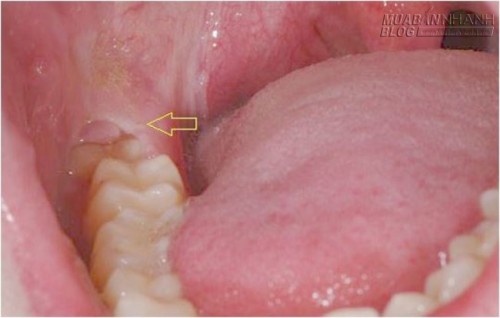

Biến chứng thường gặp khi răng khôn hàm dưới mọc lệch là viêm túi quanh răng khôn rồi lan ra mô mềm xung quanh. Mủ có thể chảy ra mặt ngoài xương hàm dưới, xuống vùng thành bên họng rồi xuống cổ.

![]()

Khi có sưng đau và hạn chế há miệng ở vùng răng khôn, bệnh nhân cần được dùng kháng sinh và các thuốc giảm đau chống viêm. Nên uống kháng sinh phổ rộng và dùng nước súc miệng thường xuyên vì trong túi lợi răng khôn thường có vi khuẩn kỵ khí.